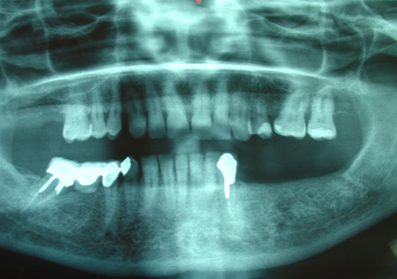

Siguiendo el protocolo de actuación, se hace la historia clínica, la ficha implantológica, se solicitan análisis de laboratorio de rutina y una ortopantomografía, así como periapicales de la zona.se toman impresiones superiores e inferiores con alginato y se vacían en yeso piedra. Se toman registros con la ayuda de un arco facial y se montan los modelos en articulador semiajustable. Después del análisis de los modelos y de las radiografías se decide colocar cuatro implantes monoblock Q-implant Trinon de 3,5 mm de diámetro y 12 mm de largo, para ser cargados de forma inmediata por un puente metal-cerámica cementado.(F1)